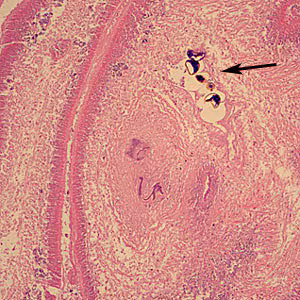

. In the definitive host, the plerocercoid develops into adult tapeworms in the small intestine. Adult diphyllobothriids attach to the intestinal mucosa by means of two bilateral groves (bothria) of their scolex

. The adults can reach more than 10 m in length, with more than 3,000 proglottids. Immature eggs are discharged from the proglottids (up to 1,000,000 eggs per day per worm) and are passed in the feces. Eggs appear in the feces 5 to 6 weeks after infection.

Mature diphyllobothriids are large tapeworms reaching 2—15 meters in length, with occasional larger specimens. The scolex always has two bothria (grooves). The general size and shape of the scolex may be subject to intraspecific variability, though some species-level differences have been described historically. Proglottids are broader than long, with a single genital pore that opens in the middle of the ventral surface; fully mature specimens may be comprised of a 2,000—5,000 proglottids. The ovaries are characteristically rosette-shaped.

Microscopic identification of eggs in the stool is the basis of family level diagnosis; genus level identification based on eggs is difficult due to overlap in morphological features. Eggs are usually numerous and can be demonstrated without concentration techniques. Identification of proglottids passed in the stool is also of diagnostic value.